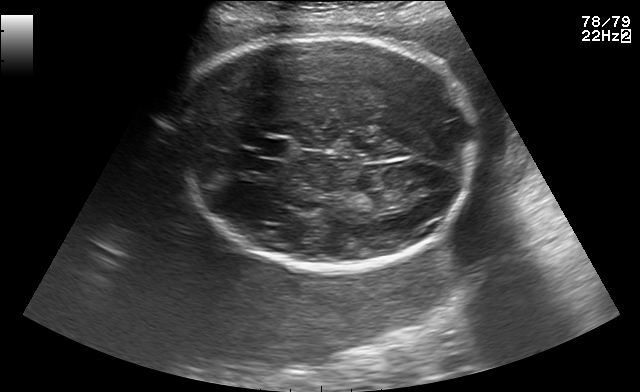

Refer to caption

(a) Fetal abdomen

(b) Fetal brain

(c) Fetal femur

(d) Fetal thorax

(e) Maternal cervix

(f) Other

Figure 1: Examples of real images in the FETAL_PLANES_DB dataset.

5.1 Visualization of Synthetic Images

The generated images were visually assessed by examining a sample of synthetic images from each of the six classes. The synthetic images were compared with the real images from the FETAL_PLANES_DB dataset in Figure 1 to evaluate their realism and similarity. Example images from the diffusion model are shown in Figure 2, where we observe that the synthetic images closely resemble the real images in terms of texture, structure, and class-specific features. This addition emphasizes the visual quality of the generated images, which was a key aspect of evaluating the success of diffusion models in this context.